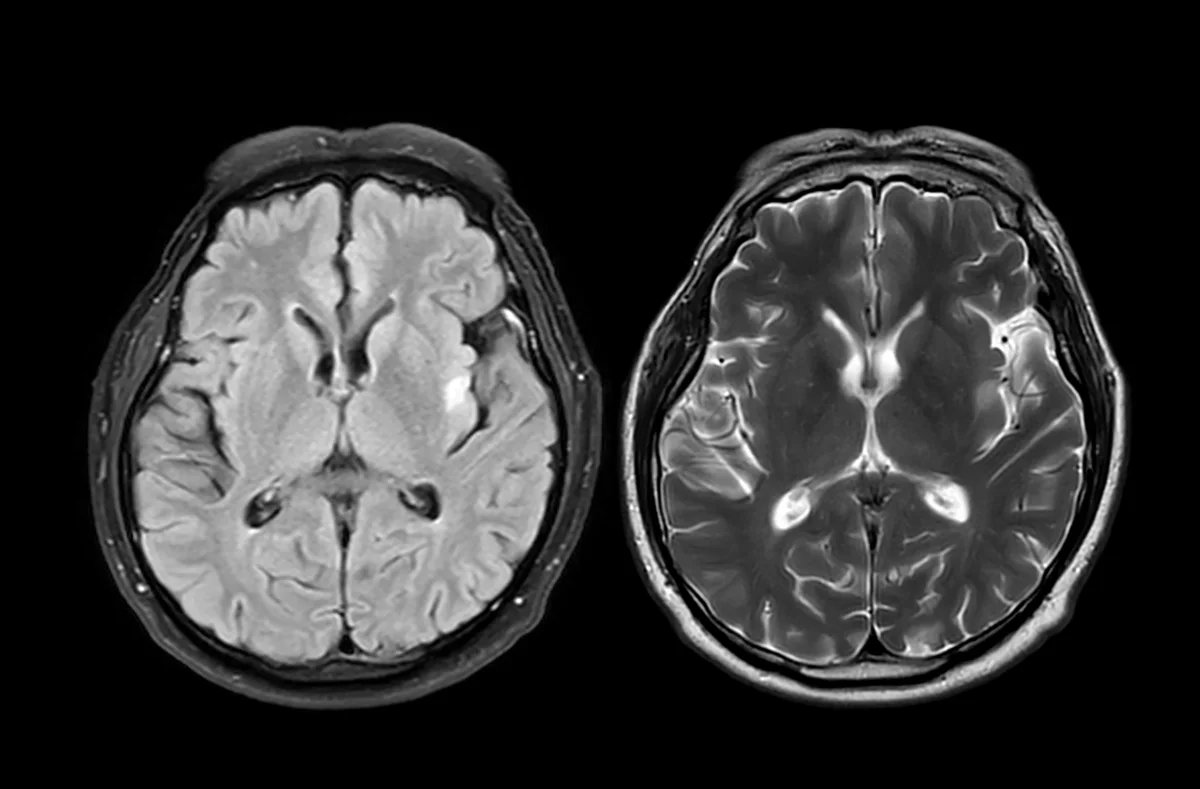

Researchers within the U.Okay. analyzed mind scans from almost 1,000 wholesome adults earlier than and in the course of the COVID-19 pandemic. What they discovered was stunning: folks residing via the pandemic confirmed indicators of accelerated mind getting older. Their brains appeared about 5 and a half months older than anticipated when in comparison with prepandemic developments.

So how did they determine this out? The scientists used information from the U.Okay. Biobank, a large well being database that features mind imaging from tens of hundreds of contributors. They educated a machine-learning mannequin to estimate “mind age” primarily based on a whole lot of structural options seen in MRI scans. Then they in contrast two teams: individuals who had each scans earlier than the pandemic and people who had one scan earlier than and one in the course of the pandemic.